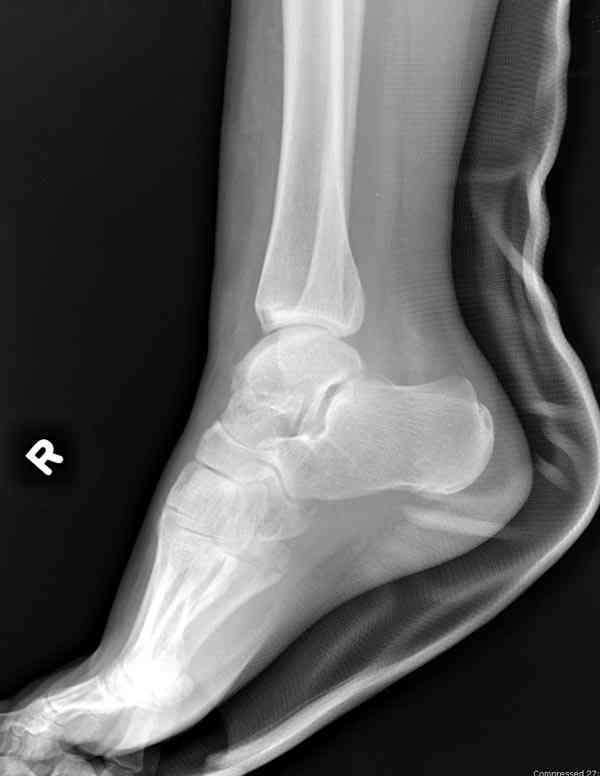

Случай с множественным оскольчатым переломом тарана оперированный из двойного доступа.

Через 14 мес.: